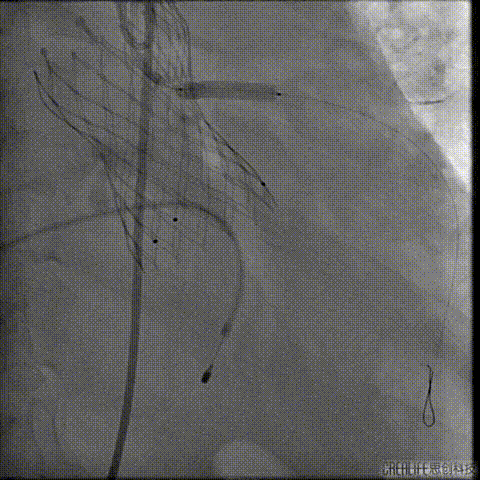

导丝跨瓣及测压

此时患者出现室速 血气提示代谢性酸中毒、高钾血症,予电复率、补碱、补镁、碘氨酮等治疗后恢复窦性心律。